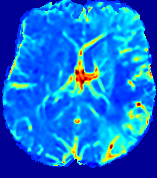

LesionRefer to captionRefer to captionRefer to captionRefer to captionRefer to captionRefer to caption𝐕rgbsubscript𝐕𝑟𝑔𝑏{\bf{V}}_{rgb}Refer to captionRefer to captionRefer to captionRefer to captionRefer to captionRefer to caption𝐕2subscriptnorm𝐕2{\|\bf{V}}\|_{2}Refer to captionRefer to captionRefer to captionRefer to captionRefer to captionRefer to captionRefer to caption3.53.53.52.82.82.82.12.12.11.41.41.40.70.70.70.00.00.0(mm/s)𝑚𝑚𝑠(mm/s)D𝐷DRefer to captionRefer to captionRefer to captionRefer to captionRefer to captionRefer to captionRefer to caption0.0200.0200.0200.0160.0160.0160.0120.0120.0120.0080.0080.0080.0040.0040.0040.0000.0000.000(mm2/s)𝑚superscript𝑚2𝑠(mm^{2}/s)Slice #1Slice #2Slice #3Slice #4Slice #5Slice #6

Figure 3: PIANO feature maps for one stroke patient, where the lesion is located in the left hemisphere. Top row: segmented stroke lesion region (white) on different slices, obtained from ISLES 2017. The corresponding slices for the PIANO feature maps are shown in the following rows.

For a better insight into an estimated velocity field 𝐕𝐕{\bf{V}} and diffusion field 𝐃𝐃{\bf{D}}, we compute the following maps: (1) 𝐕rgbsubscript𝐕𝑟𝑔𝑏{\bf{V}}_{rgb}: Color-coded orientation map of 𝐕=(Vx,Vy,Vz)T𝐕superscriptsuperscript𝑉𝑥superscript𝑉𝑦superscript𝑉𝑧𝑇{\bf{V}}=(V^{x},V^{y},V^{z})^{T}, obtained by normalizing 𝐕𝐕{\bf{V}} to unit length and mapping its 3 components to red, green, blue respectively; (2) 𝐕2subscriptnorm𝐕2\|{\bf{V}}\|_{2}: 222 norm of 𝐕𝐕{\bf{V}}; (3) D𝐷D: scalar field in Eq. 5.

Fig. 3 and Fig. 4 show the PIANO feature maps estimated from two ISLES 2017 patients: all are highly consistent with the lesion in both cases. Details of the blood flow trajectories are revealed in 𝐕rgbsubscript𝐕𝑟𝑔𝑏{\bf{V}}_{rgb} by the ridged patterns and the sharp changes of colors in the unaffected (right) hemisphere, while the flat patterns appearing within the lesion provide little directional information about the velocity and indicate low velocity magnitudes. Velocity magnitudes are more directly visualized via 𝐕2subscriptnorm𝐕2\|{\bf{V}}\|_{2}, from which one can easily locate the lesion where 𝐕2subscriptnorm𝐕2\|{\bf{V}}\|_{2} is low. D𝐷D also indicates lower diffusion values in the lesion, though with less contrast potentially due to the fact that it captures the accumulated effect of CA diffusion at the voxel-level.